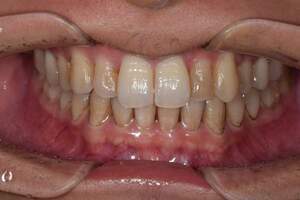

歯石除去

治療前

治療後

| 年齢 | 25歳・男性 |

| 主訴 | 歯石をとりたい・検診 |

| 治療内容 | 各種検査・歯石除去 |

| 治療期間 | 60分 |

| 費用 | 初診料3,000〜4,000円前後 +歯石除去約1,000円 |

| リスク・副作用 | ・処置後に歯がしみることがあります。 ・歯と歯の間に隙間ができるので、息が漏れ発音しにくいと感じることがあります。 ・歯ぐきの炎症が軽減すると歯ぐきが引き締まり、歯が長く見えることがあります。 |

| 担当者所見 | 前歯の裏側にすぐに歯石が溜まってしまいザラザラして気になるとご相談いただいたので適切な歯ブラシの当て方とフロスの通し方をお伝えさせて頂きました。 |